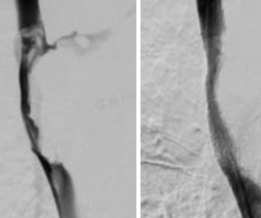

瞿大叔是一名尿毒症患者,长期在外院接受血液透析治疗。此前,为方便透析,他的左侧颈部留置了血透管。一个月前,瞿大叔拔除血透管后,发现自己左侧面部及手部出现肿胀。起初他并未重视,仅自行服用了一些消肿药物。然而一个多月过去,肿胀不仅没有消退,他还出现了声音嘶哑的症状,甚至连呼吸都受到了限制。意识到情况严重后,瞿大叔紧急来到长沙市第四医院就诊。长沙市第四医院介入血管外科副主任、副主任医师李深基为瞿大叔进行了详细检查,结合症状判断其可能存在静脉堵塞,导致静脉血无法正常回流至心脏。随后,李深基医师立即安排瞿大叔接受上腔静脉CT检查,检查结果最终证实了这一诊断——瞿大叔的左侧头臂静脉已完全闭塞,无法通过上腔静脉将血液回流至心脏。为及时打通堵塞的血管、恢复血液回流,介入血管外科团队随即为瞿大叔紧急安排了介入手术,瞿大叔很快恢复正常。

无独有偶,吴嗲嗲最近突然出现面部及双上肢明显肿胀,呼吸困难,CT提示肿瘤压迫致上腔静脉闭塞,介入血管外科为其行介入手术开通血管后,肿胀很快消退。

包括头高位休息,吸氧,使用促进静脉回流药物、适当利尿、抗凝等常规治疗。如保守治疗无效需行手术治疗,通过介入手术在上腔静脉狭窄处支架置入。该手术创伤较小、易耐受、并发症少,手术当天可下床。